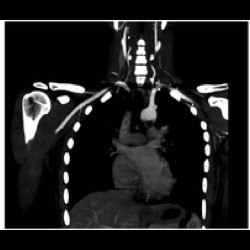

CT in detection and diagnosis of thoracic conditions in symptomatic HIV patients

CT in detection and diagnosis of thoracic conditions in symptomatic HIV patients

CT in detection and diagnosis of thoracic conditions in symptomatic HIV patients

CT in detection and diagnosis of thoracic conditions in symptomatic HIV patients